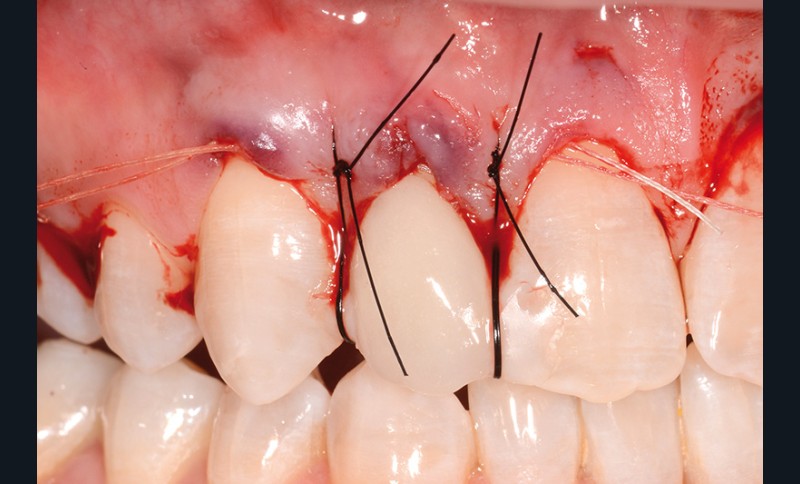

bibli/1.2.3.jpgLes points de contact sont solidarisés.

bibli/4.11.jpg_;_;_bibli/4.21.jpgLes points de contacts unis vont permettre se soutenir les sutures qui en feront le tour pour tracter le greffon coronairement.

bibli/3.3.11.jpgRevenir sous le point de contact, en faire le tour pour repasser dessous et suturer au petit chef.

bibli/3.3.21.jpgAvec ces deux sutures suspendues, le greffon est plaqué et tracté vers le collet. Les sutures résorbables distales et mésiales peuvent servir à stabiliser horizontalement.

bibli/1.2.jpgSolidarisation des points de contact avec du composite fluide pour soutenir les haubans.